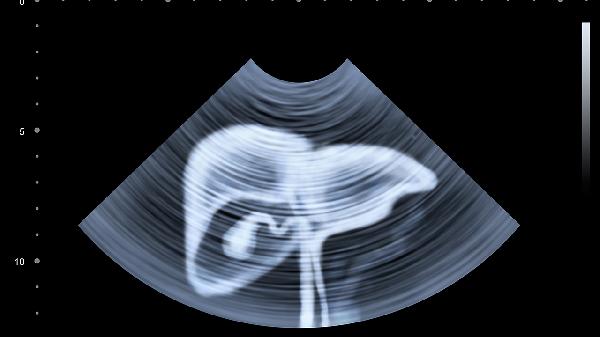

术后需监测肝功能指标、凝血功能及并发症,早期下床活动有助于预防血栓形成。高蛋白饮食可促进肝细胞再生,但需控制脂肪摄入减轻肝脏负担。定期复查超声或CT评估肝脏再生情况,避免使用肝毒性药物。出现黄疸、腹水等症状需及时就医。